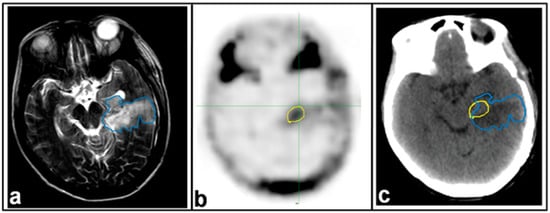

- Henriksen, O.M.; Larsen, V.A.; Muhic, A.; Hansen, A.E.; Larsson, H.B.W.; Poulsen, H.S.; Law, I. O7.08one-stop shopping in brain tumor imaging: Initial experience with PET/MR for simultaneous evaluation of tumor metabolism, structure and blood volume using 18F-fluor-ethyl-thyrosine PET and DSC-MRI. Neuro-Oncology 2014, 16, ii16–ii17. [Google Scholar] [CrossRef]

| 15 | 18F–FET | PET-DSC MRI | Evaluating tumor metabolism, structure and blood volume in the study of the human brain | Henriksen et al. [36] |